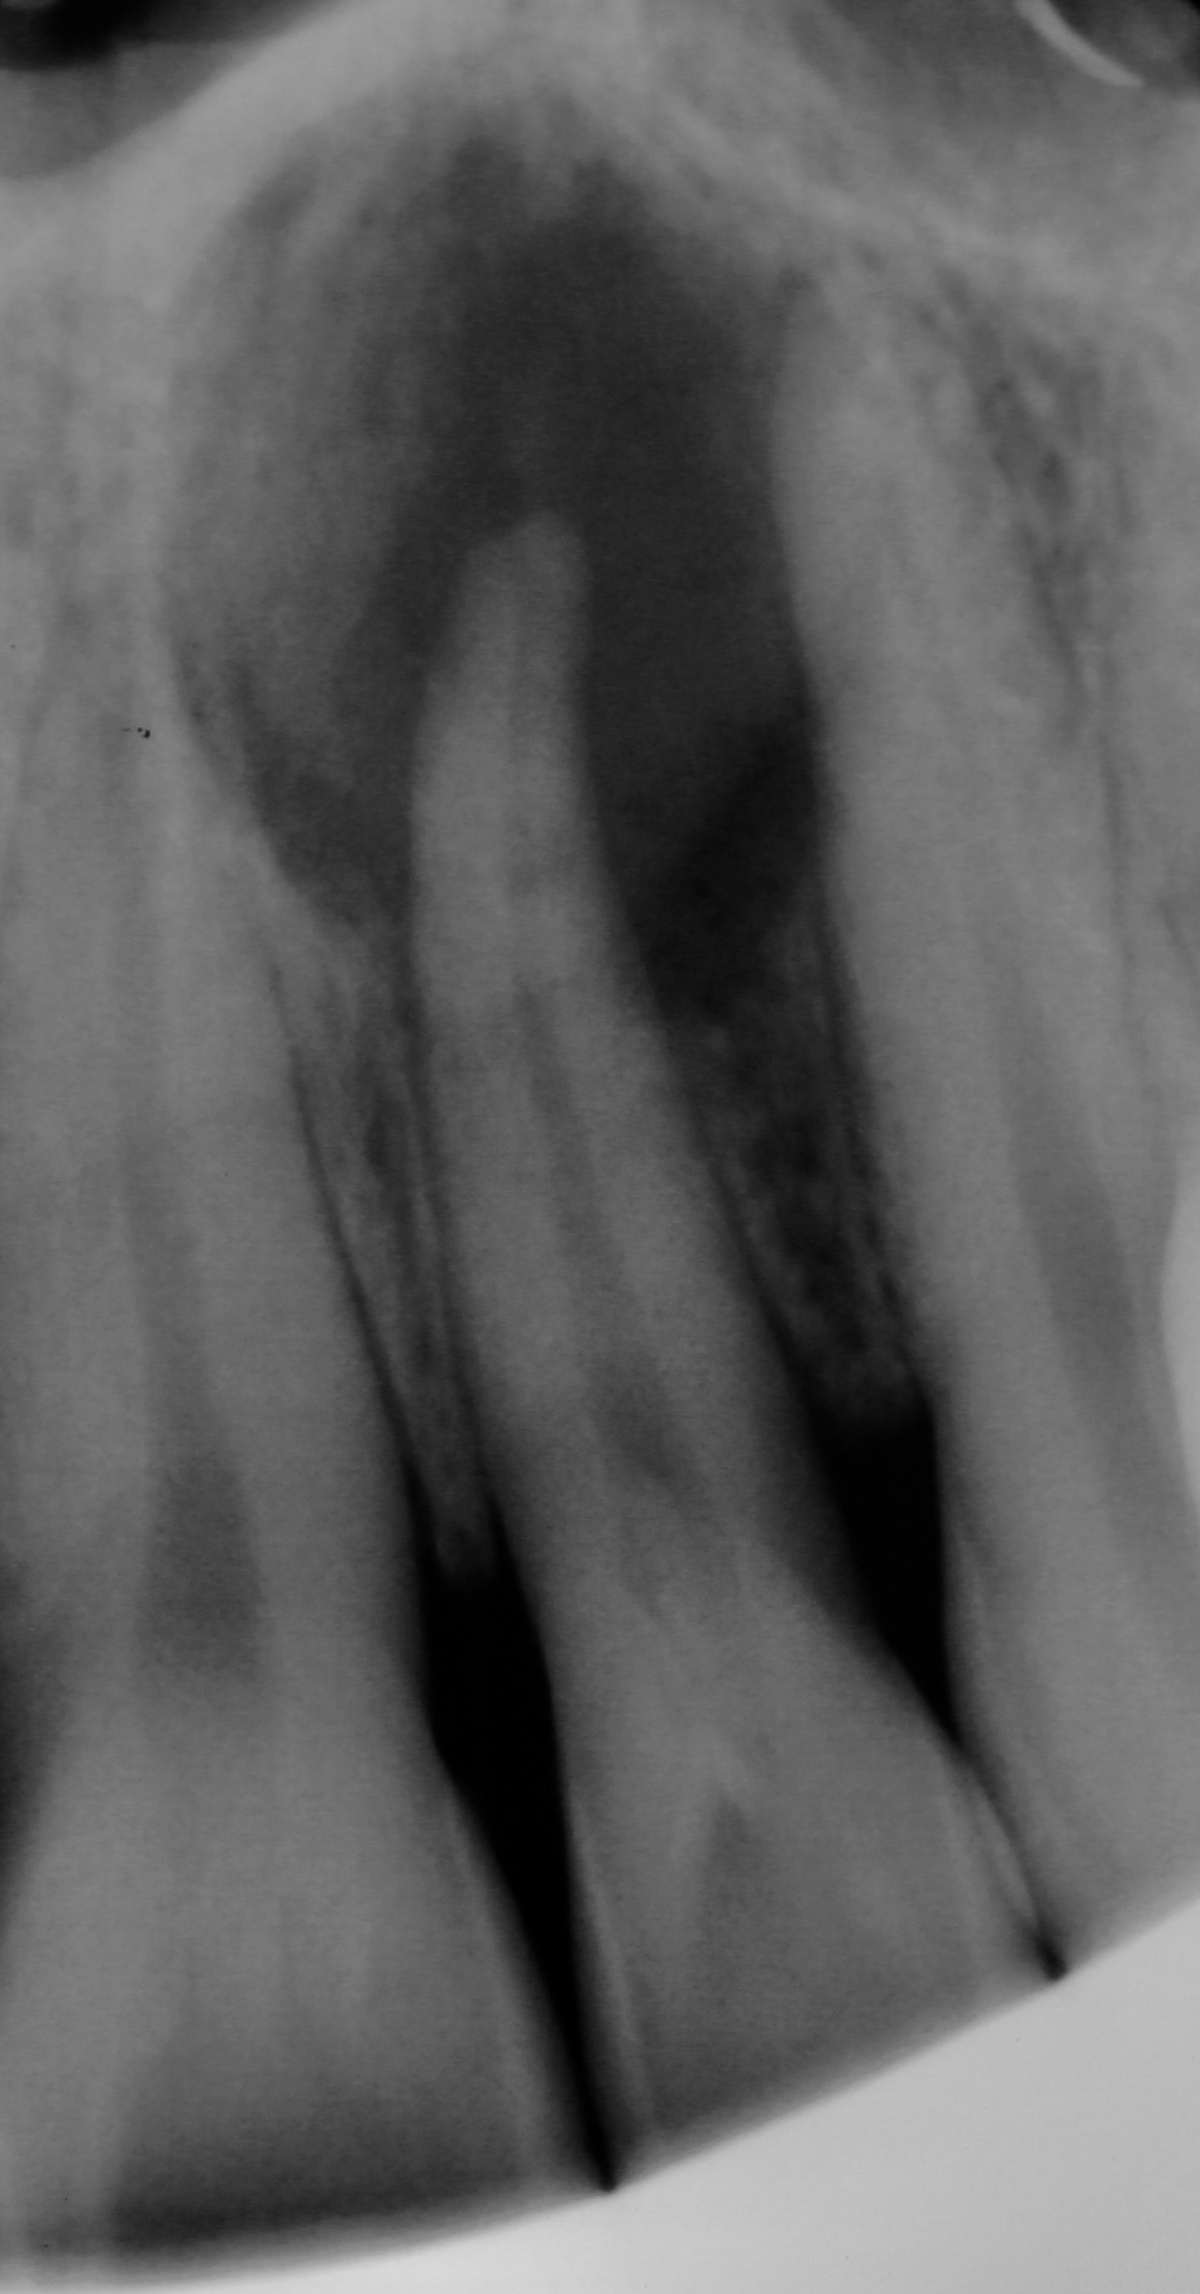

Zahn 21, Hinweise auf möglicherweise

überpresstes Wurzelfüllmaterial im apikalen Bereich.

Wurzelfüllung sowie Hinweise auf eine vorhandene

Via falsa.

Im Januar 2019 stellte sich ein 52-jähriger Soldat mit einem auf Gingivaniveau abgebrochenen Zahn 21 im Rahmen einer Notfallbehandlung bei uns vor. Zur Wiederherstellung der Ästhetik, Phonetik und Beißfunktion wurde die Krone in direktem Verfahren wieder aufgebaut. Das anschließend angefertigte Röntgenbild zeigte eine zu kurze und inhomogene Wurzelfüllung mit Hinweisen auf eine vorliegende Via falsa.

Gleichzeitig berichtete der Patient über Beschwerden am Zahn, welche wiederholt auftraten und sich durch Druck auf das Vestibulum reproduzieren ließen. Eine Schwellung, Fistelung oder erhöhte Sondierungswerte lagen zu diesem Zeitpunkt nicht vor. Da zur Aufnahme einer laborgefertigten Restauration eine vorherige Stiftinsertion geplant war, vereinbarten wir zunächst die Revision der vorhandenen insuffizienten Wurzelfüllung. Trotz Dentalmikroskop und vorgebogenen Ultraschallfeilen ließ sich der ursprüngliche Kanalverlauf während der Revisionsbehandlung nicht mehr darstellen (Abb. 3 zeigt den Verlauf der Via falsa).